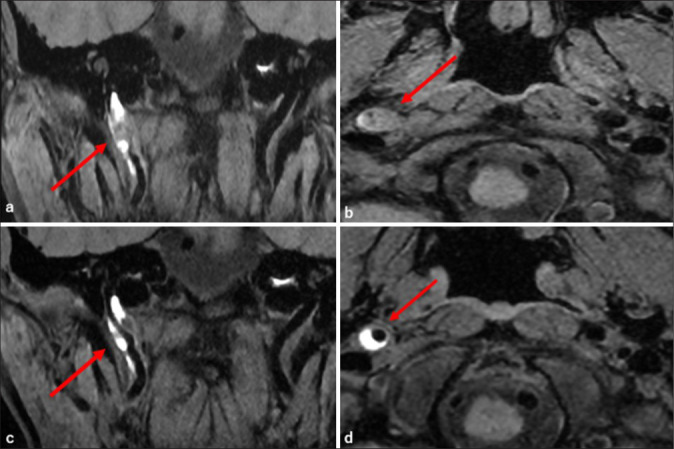

Case description: We report the case of a 45-year-old woman who presented with isolated right-sided glossopharyngeal nerve symptoms - specifically, ageusia and pharyngeal discomfort - along with mild posterior neck pain. Initial evaluation by otolaryngology failed to identify the etiology. Subsequent imaging at our hospital revealed a spontaneous dissection of the right internal carotid artery extending from the third cervical spinal cord level to the proximal petrous segment. Magnetic resonance angiography and digital subtraction angiography confirmed the diagnosis of ICAD. Conservative management with antiplatelet therapy (aspirin 100 mg/day) led to symptom improvement, and follow-up imaging after 180 days demonstrated near-complete resolution of the dissection.

Conclusion: This case is noteworthy due to the absence of cerebral ischemic findings and the isolated involvement of the glossopharyngeal nerve, likely due to localized anterolateral expansion of the dissection cavity compressing the pharyngeal branch of the nerve. Although mild styloid process elongation was observed, there was no radiological evidence suggesting Eagle syndrome. This case emphasizes the importance of considering ICAD in the differential diagnosis of lower cranial nerve palsies, even in the absence of stroke or typical neurological signs.